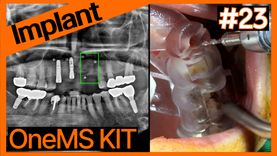

Implant placement with OneMS KIT on maxillary anterior GB...

온라인서저리2025-10-13T00:00